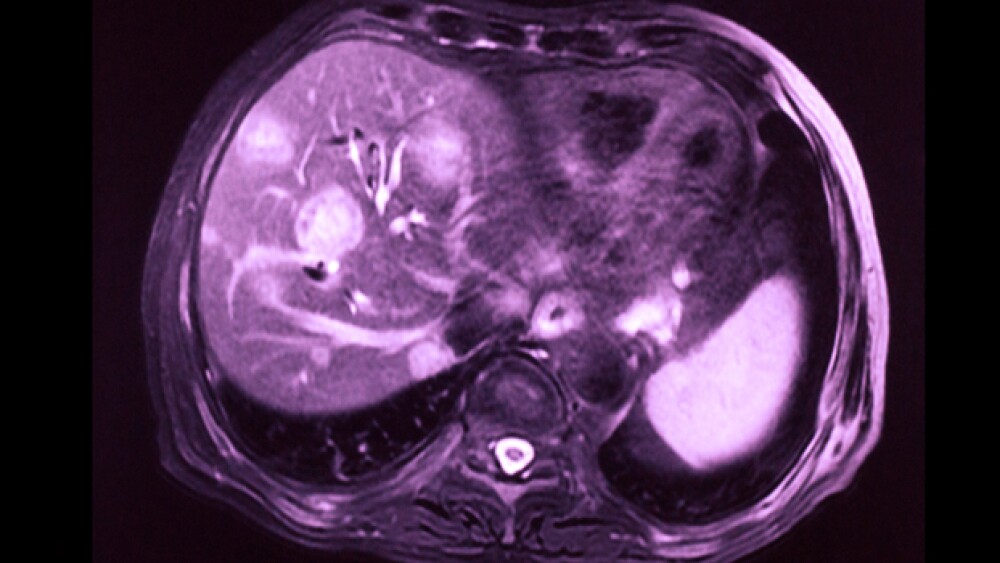

• Magnetic resonance imaging (MRI) scans provide detailed images of soft tissues in the body by using radio waves and strong magnets instead of x-rays. Sometimes they can tell a benign tumor from a malignant one. They can also be used to look at blood vessels in and around the liver to see any blockages and can help show if liver cancer has spread to other parts of the body.